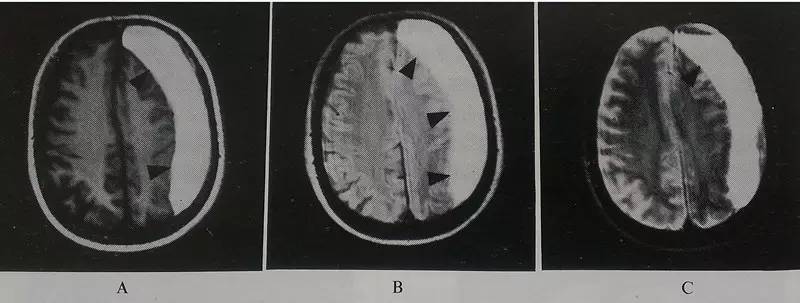

若撞击力度较轻,脑部在CT上没有肉眼可见的异常,脑细胞仍存在微损伤,功能会发生障碍:若出现短暂昏迷,时间在30分钟内;清醒后,回忆不起受伤时的情景,但能清楚记得受伤前的事情;同时,还有头痛、头晕、恶心、厌食、呕吐、耳鸣、注意力不集中、反应迟钝等症状,血压、呼吸和脉搏、神经系统和脑部CT检查正常,这种情况,医生通常会诊断为脑震荡。